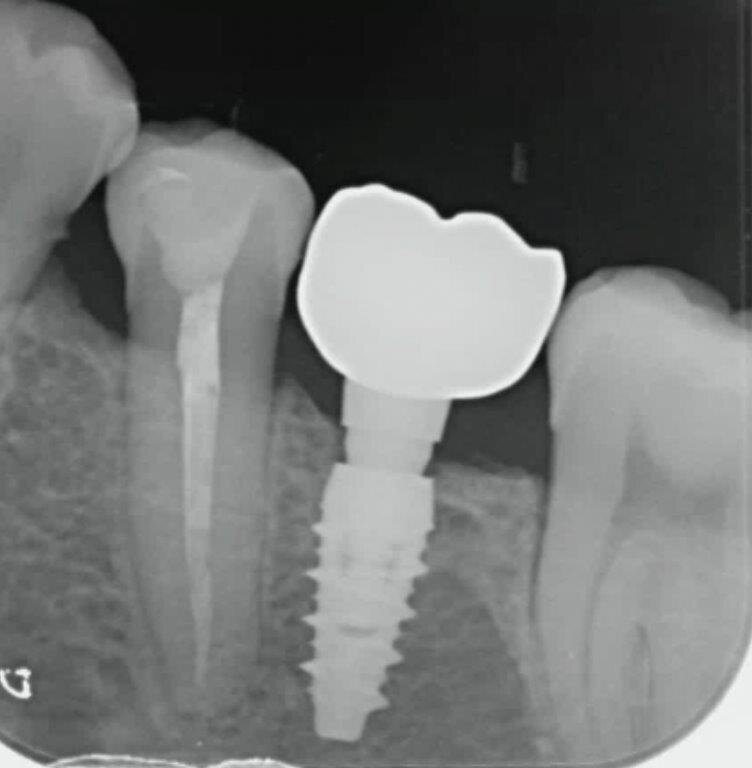

Nello studio sono stati inclusi 20 pazienti (12 donne e 8 uomini) di età compresa tra i 28 e i 65 anni, con edentulia singola e conseguente deficit vestibolare dei tessuti molli. La matrice dermica a elevata consistenza è stata opportunamente ritagliata mediante forbici e lama ed è stata posizionata al di sotto del lembo muco periostale allestito con approccio a spessore totale, vestibolarmente alla cresta ossea in cui è stato posizionato contestualmente un impianto endosseo osteointegrabile. Non si è utilizzato alcun ausilio di fissazione per la matrice dermica che è stata stabilizzata dal solo lembo di accesso ribaltato su di essa e suturato, mediante punti staccati semplici, al lembo linguale.

Le rilevazioni eseguite a distanza di 18 mesi di tempo medio, hanno mostrato un netto miglioramento del PES (Pink Esthetic Score) con un punteggio medio superiore a 9 (eccellente) e in due casi un punteggio tra 6 e 8 (buono). La sovrapposizione dei file .stl provenienti dalla scansione della arcata dentaria interessata prima dell’intervento e a distanza di 18 mesi ha permesso di rilevare un incremento medio in senso orizzontale di 2 mm in media.